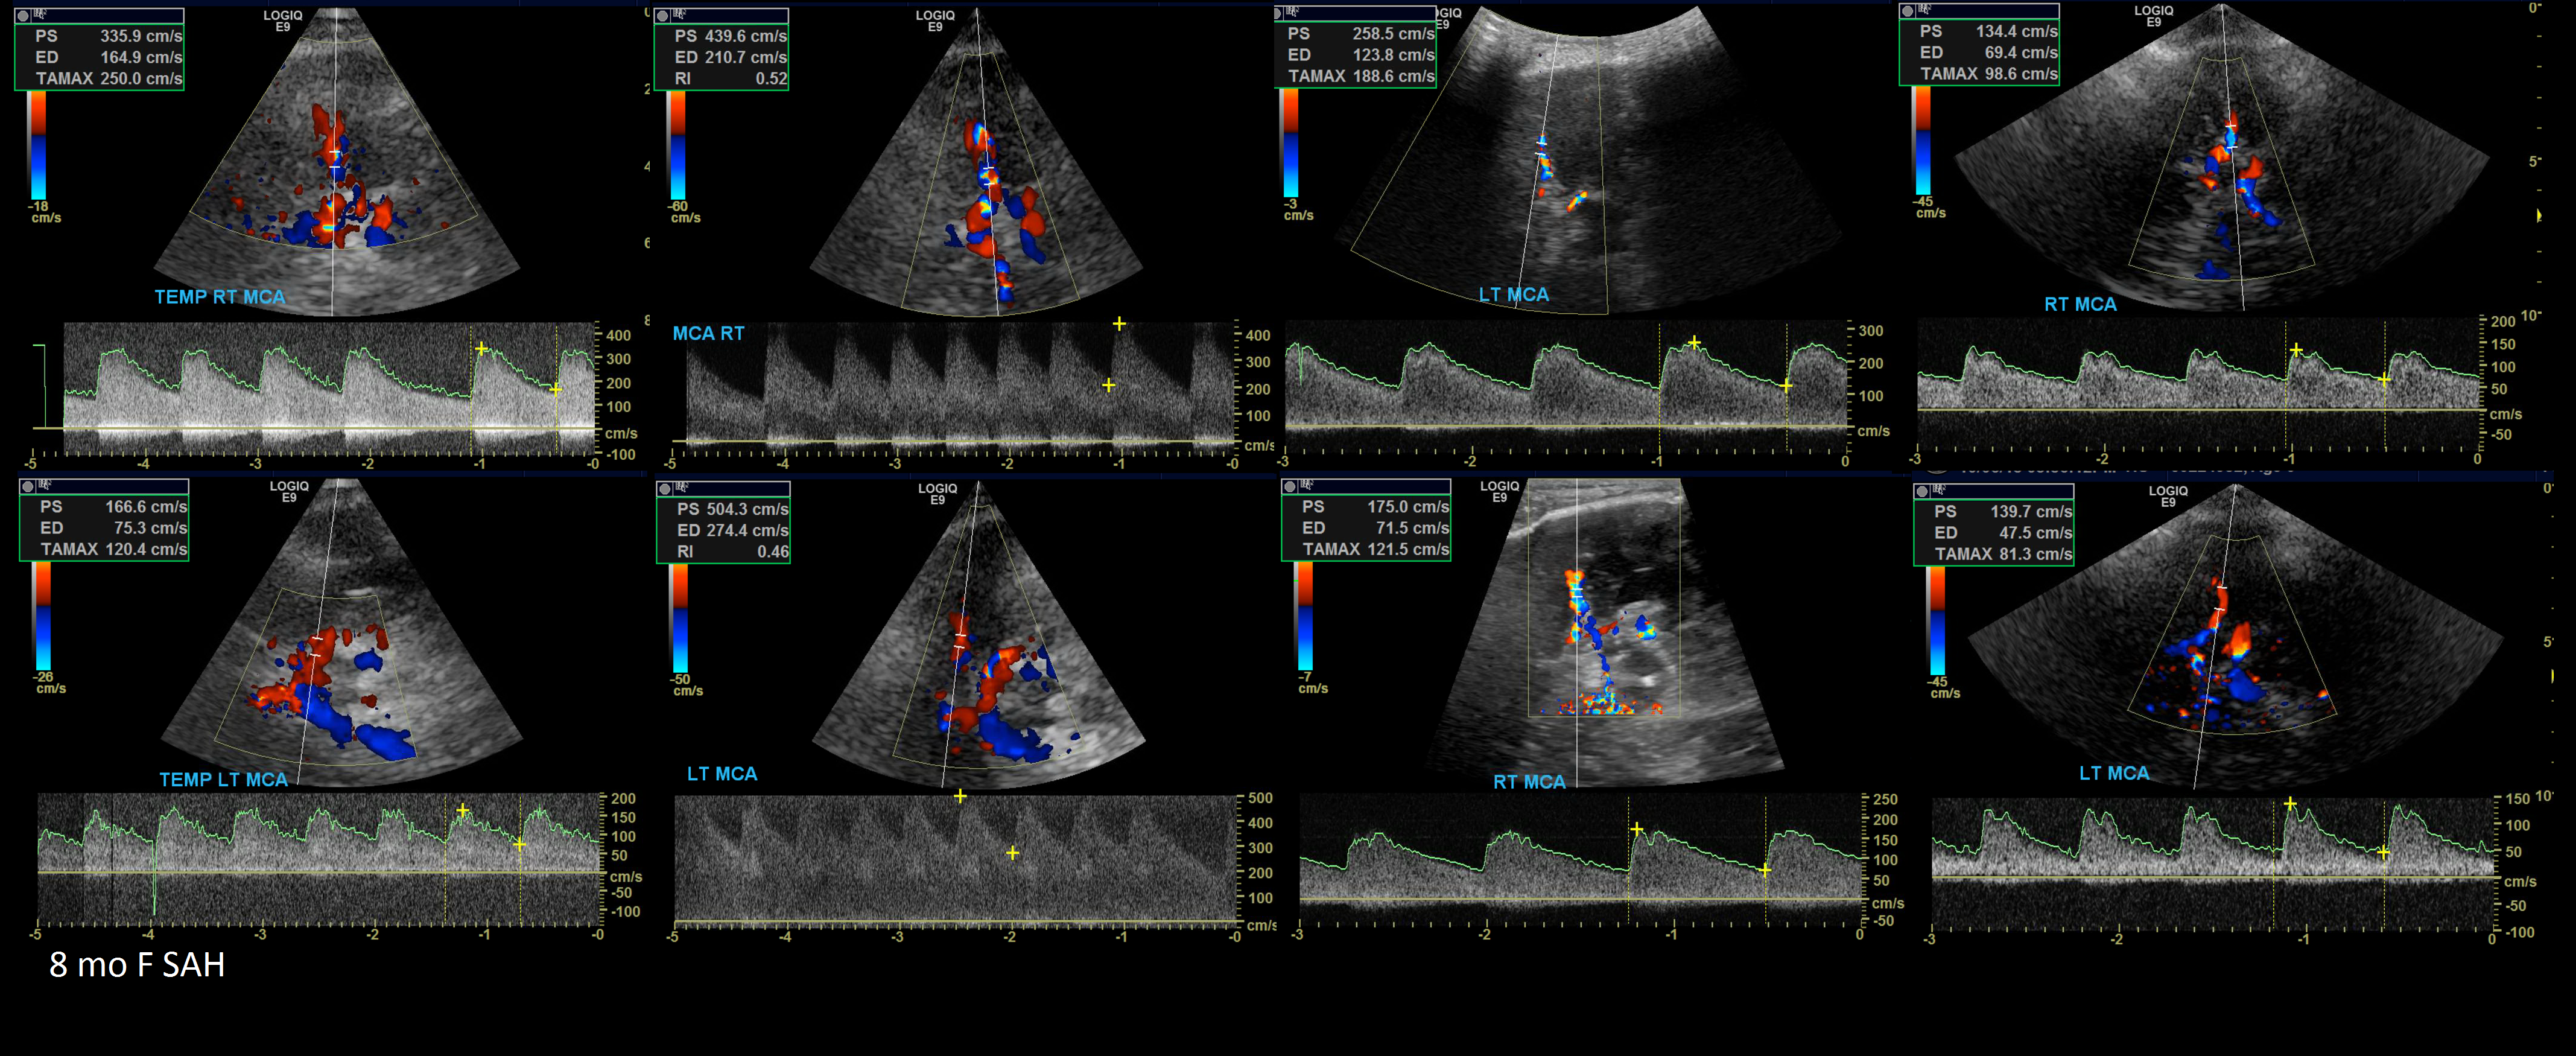

Vasospasm Criteria

8 month old F fall that caused a Subarachnoid Hemmorhage. Serial TCD’s show progression of vasospasm.